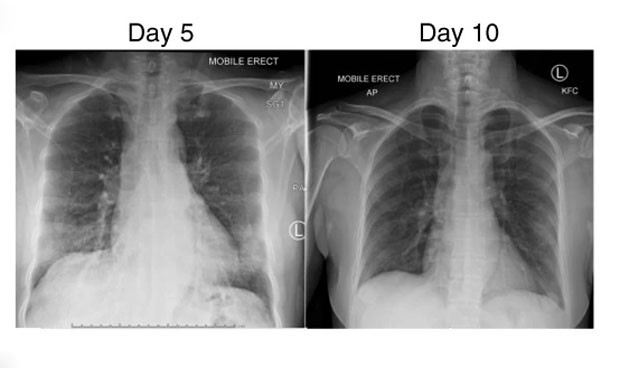

Imagen de los pulmones de la paciente. Fuente: Nature.

El caso estudiado se trata de una mujer de Wuhan, de 47 años, que viajó a Australia procedente de Hubei. "No tuvo contacto con el mercado de mariscos de Huanan ni con casos conocidos del virus COVID-19. Por lo demás, estaba sana, no fumaba y no tomaba medicamentos", detallan.

Una vez detectado el SARS-CoV-2 mediante una PCR, los profesionales constataron que no tenía otras patologías por lo que "su manejo fue la rehidratación de líquidos intravenosos sin oxigenación suplementaria. No se administraron antibióticos, esteroides o agentes antivirales", apuntan.

"Fue dada de alta al aislamiento domiciliario el día 11. Sus síntomas se resolvieron por completo el día 13 y permaneció bien en el día 20, con aumentos progresivos en los anticuerpos IgM e IgG de unión al SARS-CoV-2 en plasma desde el día 7 hasta el día 20".

Con los síntomas del coronavirus "esta paciente no experimentó complicaciones de insuficiencia respiratoria o síndrome de dificultad respiratoria aguda, no requirió oxigenación suplementaria y fue dada de alta una semana después de su hospitalización, consistente con enfermedad no grave pero sintomática".